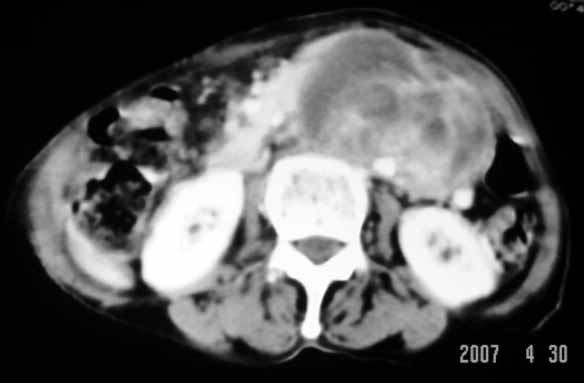

以下是引用天南地北在2007-4-30 17:42:00的发言:[br]增强扫描显示腹主动脉给包绕、推移。肿块不规则强化,[br]修正我在平扫的诊断[br]支持考虑:间叶源性肿瘤可能性大

以下是引用余辉在2007-4-30 18:01:00的发言:[br]病灶前方的条状增强影是什么?若是胰腺,位置似乎有点低,若是十二指肠,似乎又不诫该是那样强化,姑且将其看作胰腺吧,那么考虑来源于胰腺粘液囊腺瘤可能性大,其次考虑来源于肠系膜或者后腹膜的肿瘤如平滑肌肉瘤,异位嗜铬细胞瘤及淋巴瘤等。

以下是引用zyx168在2007-4-30 23:24:00的发言:[br]考虑:间叶源性肿瘤可能性大